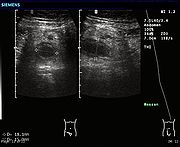

Ultrasonography and Doppler sonography provide useful means to detect appendicitis, especially in children. In some cases (15% approximately), however, ultrasonography of the iliac fossa does not reveal any abnormalities despite the presence of appendicitis. This is especially true of early appendicitis before the appendix has become significantly distended and in adults where larger amounts of fat and bowel gas make actually seeing the appendix technically difficult. Despite these limitations, in experienced hands sonographic imaging can often distinguish between appendicitis and other diseases with very similar symptoms such as inflammation of lymph nodes near the appendix or pain originating from other pelvic organs such as the ovaries or fallopian tubes.